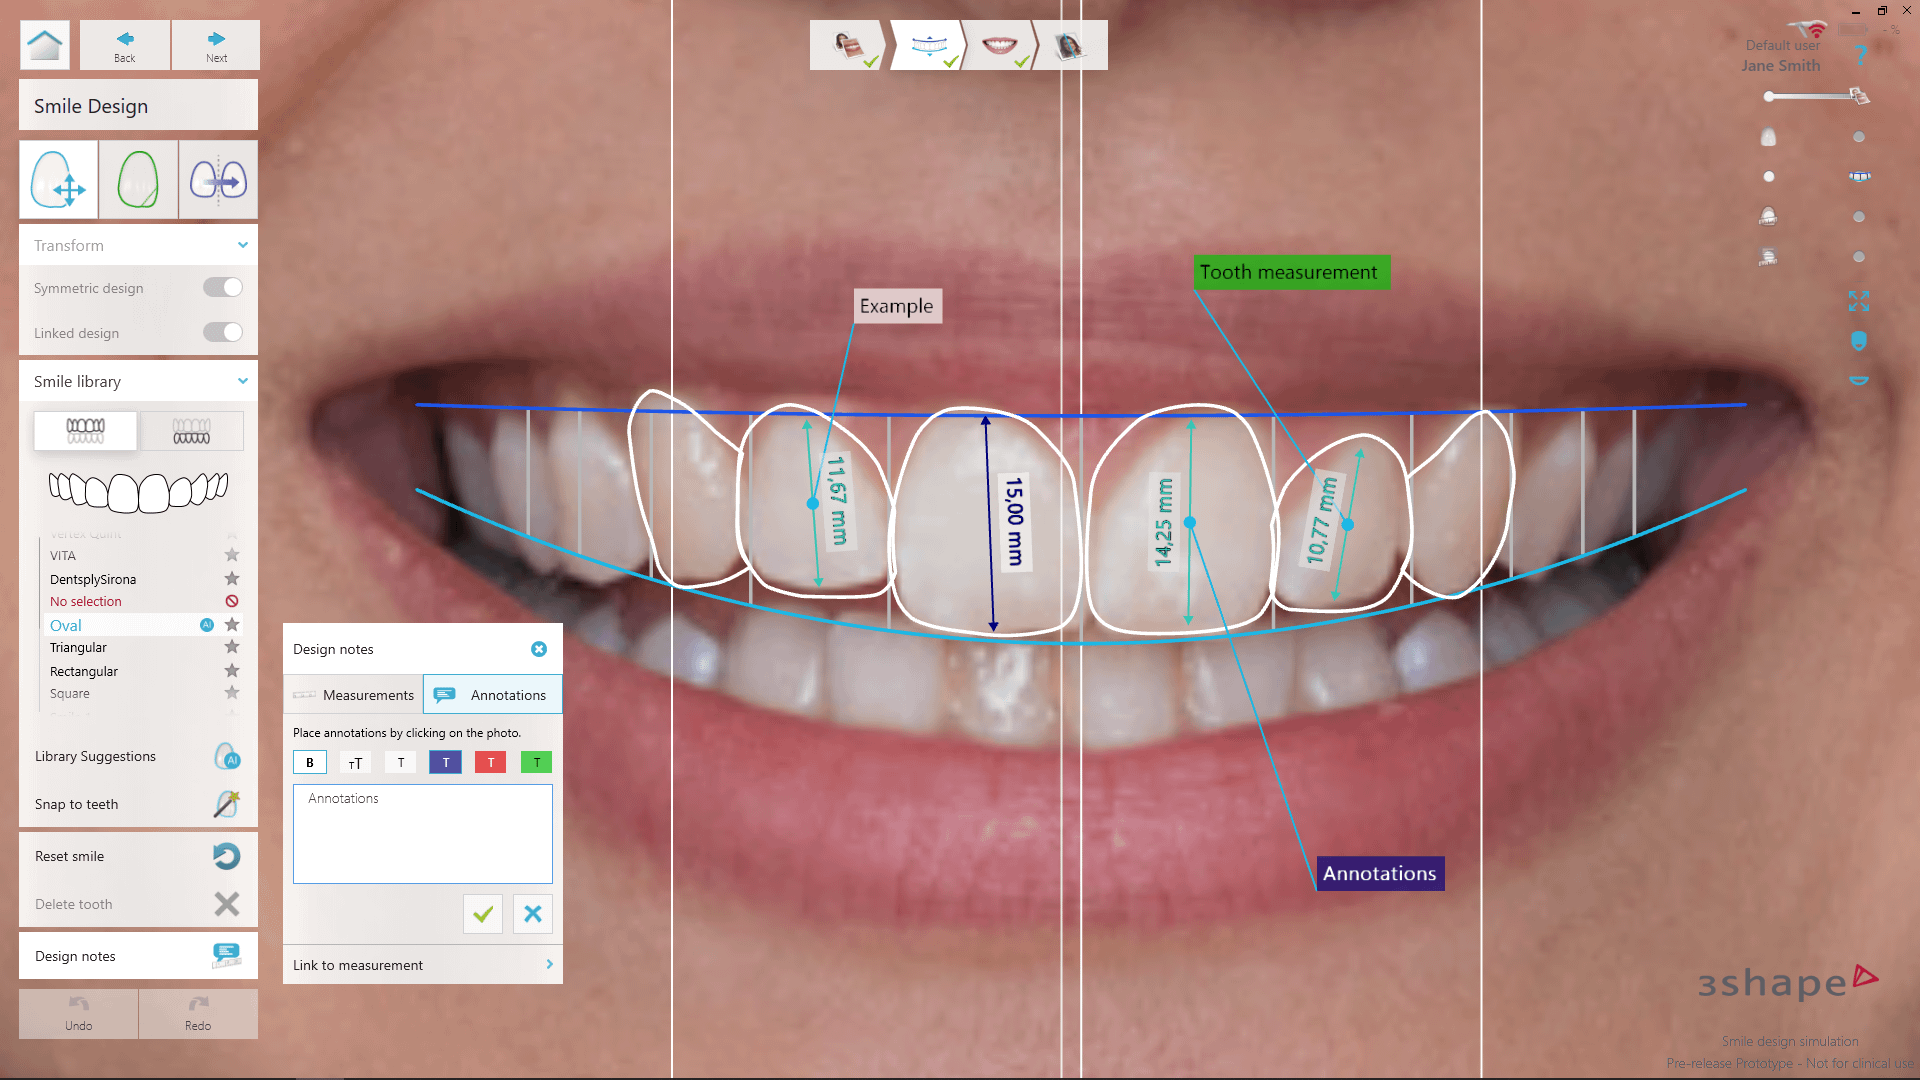

3shape Smile Design

Immerse yourself in the artistic beauty of 3shape Smile Design through substantial collections of inspiring images. blending traditional techniques with contemporary artistic interpretation. transforming ordinary subjects into extraordinary visual experiences. The 3shape Smile Design collection maintains consistent quality standards across all images. Ideal for artistic projects, creative designs, digital art, and innovative visual expressions All 3shape Smile Design images are available in high resolution with professional-grade quality, optimized for both digital and print applications, and include comprehensive metadata for easy organization and usage. Our 3shape Smile Design collection inspires creativity through unique compositions and artistic perspectives. Instant download capabilities enable immediate access to chosen 3shape Smile Design images. Our 3shape Smile Design database continuously expands with fresh, relevant content from skilled photographers. The 3shape Smile Design collection represents years of careful curation and professional standards. Diverse style options within the 3shape Smile Design collection suit various aesthetic preferences. Multiple resolution options ensure optimal performance across different platforms and applications. Professional licensing options accommodate both commercial and educational usage requirements. Each image in our 3shape Smile Design gallery undergoes rigorous quality assessment before inclusion. Time-saving browsing features help users locate ideal 3shape Smile Design images quickly. Advanced search capabilities make finding the perfect 3shape Smile Design image effortless and efficient.